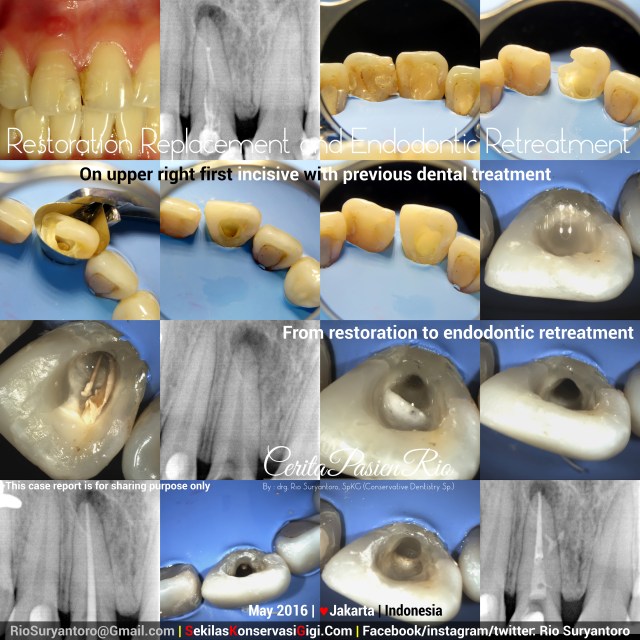

Restodontic: Restoration Replacement and Endodontic Retreatment

This patient might feel bad day for years, its gum kept on running a yellowish fluid, and this patient also could not open its mouth while smiling because a blackening-joined composite resin filling on anterior teeth..

Xray examination showed a bone loss under endodontically treated upper right first incisive. This failed previous endodontic treatment need to be fixed before heading to anterior restoration.

After taking proper informed consent, i did access cavity, removing the previous filling, and rebuild the missing wall with packable composite (filtek Z350xt from 3M) and Greater Curve matrix. Then, i dissolve the gutta percha with eucaliptus oil. Cleaning and shaping was done with ProtaperNext (Dentsply) and Natrium Hypochlorite 5,24%. After obturation, the orifice was coronally sealed with low_shrinkage_stress flowable composite (filtek_bulkfill flowable from 3M). Xray examination with Vistaray 7.1 (Durr) at 60kV, 3mA, 0,03 seconds showed an obturation with lateral canal..